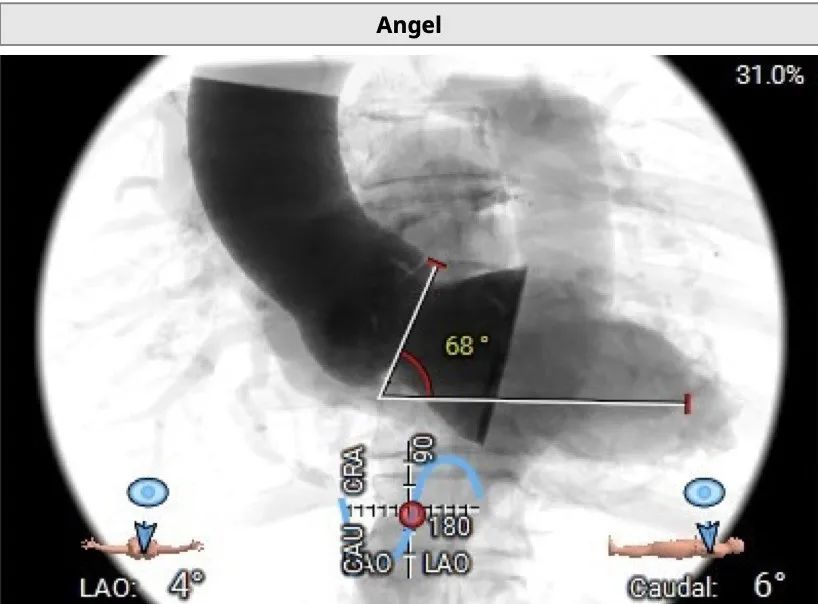

术中建议造影角度LAO 4°,CAU 6°(其它考角度如下图):

横位心,心室角度68°: